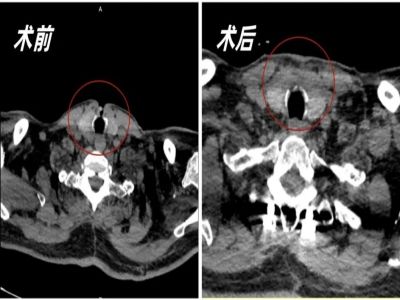

入院后,在浙江大学康复医院医疗副院长兼重症医学科主任张庚的组织下,召开了多学科团队(MDT)讨论会,并制定了相应的手术方案。准备就绪后,由大外科主任金心为患者实施了“气管造口闭合+阔筋膜切除+气道修补术”。术后进行一系列的康复治疗成功拔管,目前患者的各项指标均处于正常范围。

气管造口术,又称为气管切开术,是一种经皮切开颈段气管,放入气管切开套管以建立人工气道的创伤性操作,其目的主要是维持气道通畅、连接呼吸机和进行气道内操作等。

气管切开是危重患者救治过程中常用的措施,但术后患者如得不到规范管理,易导致相关并发症,气管造口瘘便是其中一种。